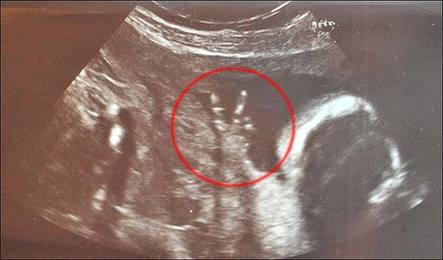

中国日报网环球在线消息: 这恐怕是世界上最自信狂野的宝宝——他(她)还在妈妈肚子里时就比出了完美的V字型手势,仿佛在向世人宣称:“嘿,我可就要来到世上了哦,准备接招吧各位!”

据英国《太阳报》7月9日报道,怀孕已经23周的英国女子卡洛琳•巴恩斯近日来到医院做定期的超声波检查,结果发现肚子里的宝宝居然从始至终都竖着两根小手指头,摆出了绝对到位的V字型手势。

今年35岁的卡洛琳为伦敦当地的一家电视台工作,她告诉记者:“在场的护士都笑个不停。做检查的整个过程中,宝宝的手势一直都是那样。”